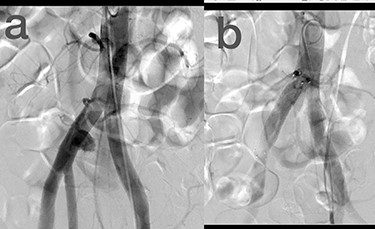

Sites of injury included 6 Posterior Tibialis arteries (27.2%) (Fig. 1), 2 deep femoral arteries (9.09%), 2 Superficial femoral arteries (9.09%) and 2 maxillary arteries (9.09%). We had only one injured artery (4.54%) in each of the following sites: internal pudendal a., Axillary a. (Fig. 2), Proneal a., Lumbar a., External carotid a., Anterior Tibialis a., common iliac a. (Fig. 3), temporal a., Thoracic aorta and Internal iliac artery (Fig. 4).

(a) Branch of Axillary artery before intervention, (b) after coil embolization.